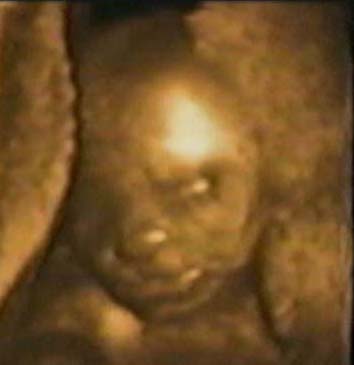

William2.jpg, 17/11/2003, 21 kB